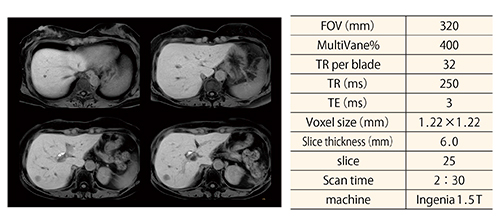

(1) 肝臓MRIにおけるT2WI turbo spin echo法は,複数回の息止め,呼吸同期法,横隔膜同期法が用いられるが,患者の呼吸状態により腹壁脂肪によるゴーストアーチファクト発生をしばしば経験する。このように,呼吸運動制御不能な場合にMV XDを呼吸同期に併用することで,腹壁脂肪によるアーチファクトを低減した画像取得を可能とした(図2)。

図2 呼吸同期併用T2WI-MV XDの画像 肝臓Gd-EOB-DTPA

MRI検査における呼吸同期併用T2WI-MV XD画像である。腹壁脂肪のゴーストアーチファクトのない画像の取得が可能である。

(画像ご提供:王子総合病院様)